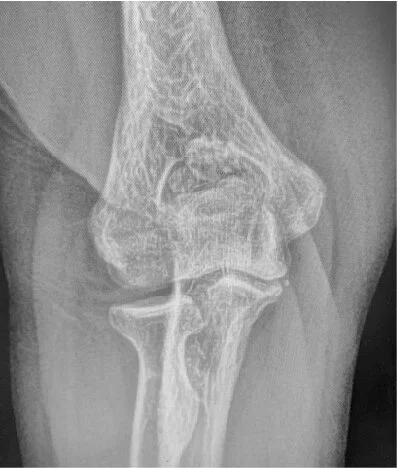

The patient presented complaining of chronic posterior right elbow pain for years with a sense of intermittent locking of her joint. Her symptoms have gradually worsened and have become functionally significant. She denied any traumatic event and has no known history of inflammatory arthritis. Her physical exam was notable for a 10-degree elbow flexion contracture with a mild effusion and mild deep midline posterior elbow tenderness. Her orthopaedic exam was otherwise unremarkable. Preoperative plain films and MRI are shown below.